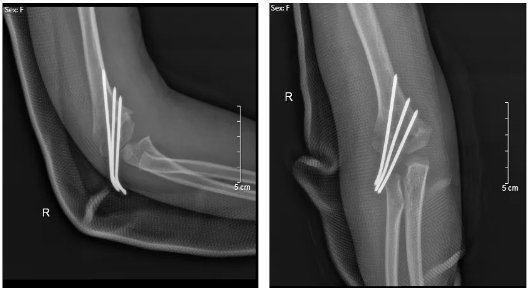

手术过程顺利,用时仅30分钟,术后拍片见克氏针分布合理,骨折复位良好,患儿肘部疼痛、肿胀等症状明显好转,家属对手术疗效也表示满意,术后两日就办理出院。

术后X线复查